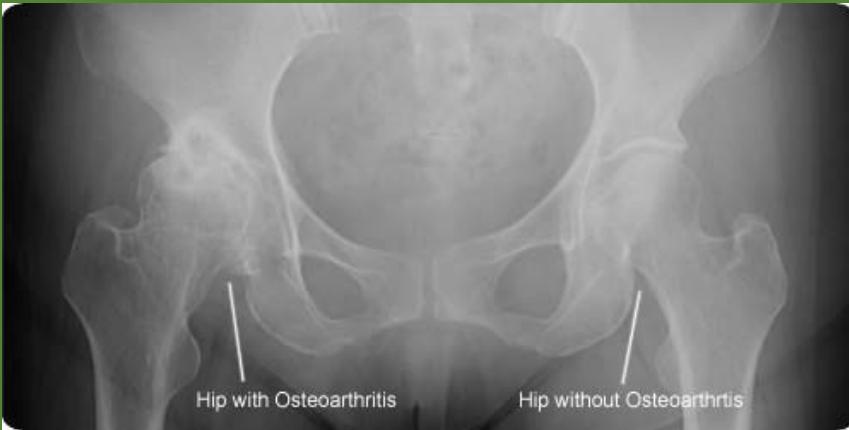

Hip osteoarthritis comparison images: * Hip without Osteoarthritis (for comparison)